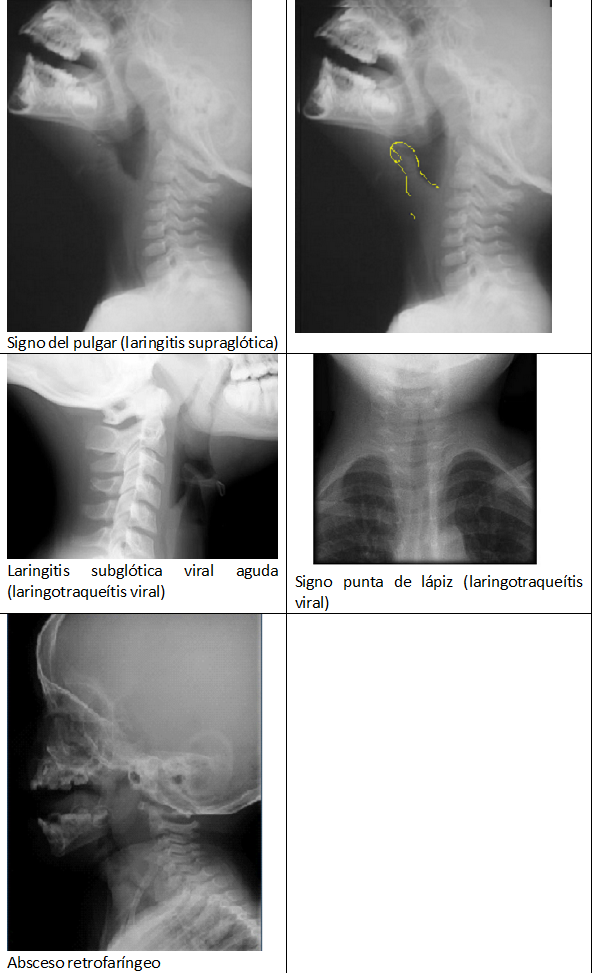

.- Rx de cavum faríngeo en laringitis supraglótica o epiglotitis: Epiglotis engrosada con “signo del pulgar”, engrosamiento de pliegues aritenoepiglóticos y ensanchamiento de hipofaringe.

.- Rx lateral de cuello en laringitis subglótica viral o laringotraqueítis viral: Ensanchamiento de hipofaringe, estrechamiento subglótico, con cuerdas vocales irregulares y engrosadas.

.- Rx anteroposterior de cuello en laringotraqueítis viral: Laringe que finaliza en punta o  “signo en punta de lápiz”.

.- Rx lateral de cavum faríngeo en abscesos retrofaríngeo y periamigdalinos: aumento de partes blandas radiopacas retrofaríngeas (sin aire en su interior) que desplaza la VAS hacia adelante.